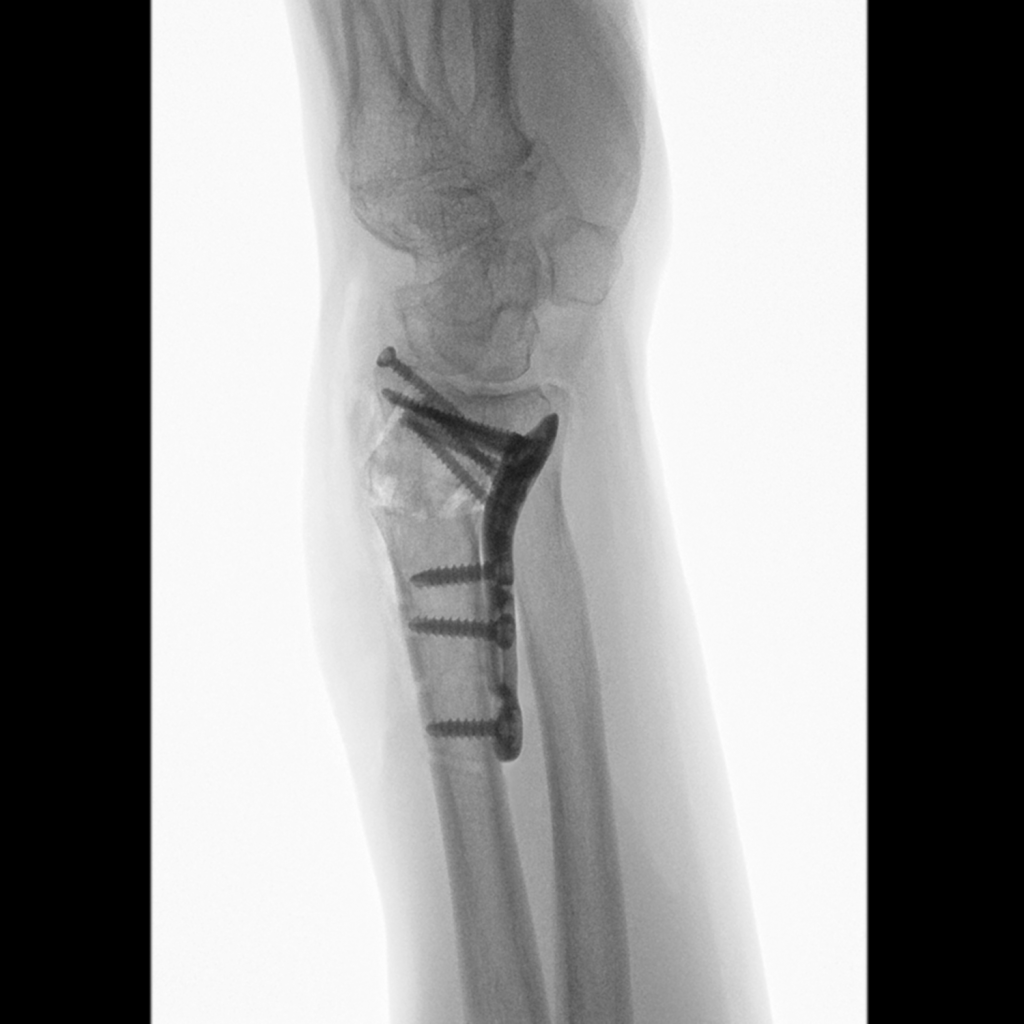

The hand surgery team operates on 12 to 16 cases per week in three of eight operating rooms. Additionally, patients come in for consultations. On average, two to four people with climbing injuries seek advice each week. “For example, they want a realistic assessment of when they will be able to climb again if their general practitioner says it is no longer possible,” explains the hand surgeon. “In fact, we operate on only a handful of them each year because most climbing injuries can be treated without surgery.” Prof. Schweizer and his team most frequently operate on people with carpal tunnel syndrome and fractures. They also often perform corrective osteotomies. These are necessary when fractures have not been treated or have been treated inadequately. If the forearm bones grow together incorrectly, it can lead to restricted movement and pain. During a corrective osteotomy, the surgeon sections the affected bone so that the pieces can be repositioned and secured with screws in proper alignment. “In complex cases, planning such an operation can take several hours,” emphasizes Prof. Schweizer. To ensure the bones are precisely fitted together at the correct angle, the hand surgeon uses computer assisted research and development (CARD) blocks customized for each patient. Based on a Japanese model, the physician developed these 3D-printed templates himself and introduced them at Balgrist. They facilitate precise sawing and screw placement. Operations using CARD blocks now take place weekly, setting the university hospital apart from other institutions. “Depending on the case, we are 30 to 50 percent faster. A shaft osteotomy takes only two hours instead of four,” explains Prof. Schweizer.

Working closely with his surgical team, Prof. Schweizer takes advantage of the technologies at his disposal: These include 3D blocks and mini C-arms, which provide reliable images for checking the position of bones, wires, screws, and plates. For Prof. Schweizer, his work and hobby go hand in hand because “When operating, it’s definitely an advantage to have a bit of strength.” His good finger strength enables him to sustain his body weight on even the smallest climbing handholds, as well as to safely and precisely guide surgical instruments during procedures.